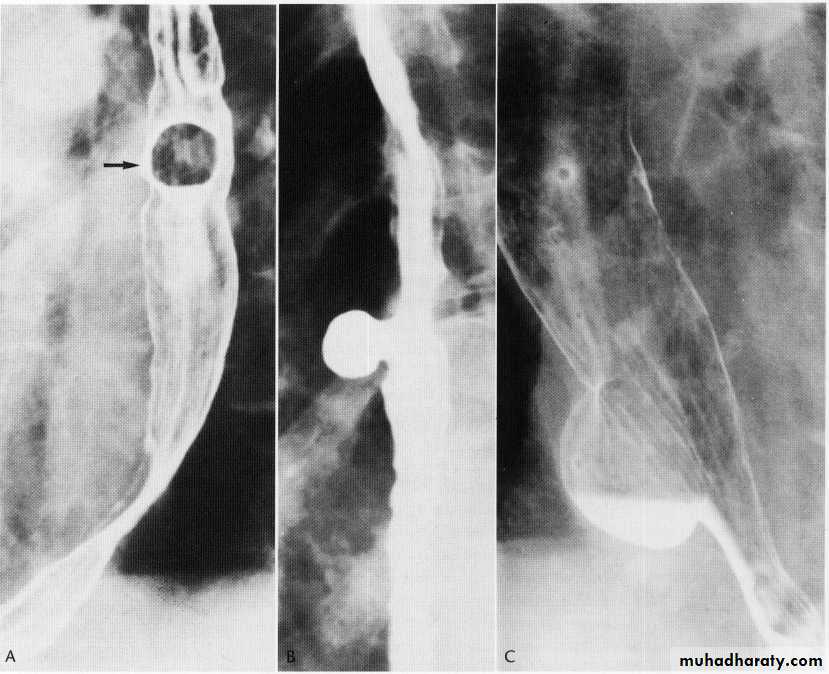

Esophageal tumours lyomyoma

Leiomyoma EUS

Leiomyoma Ba swallow